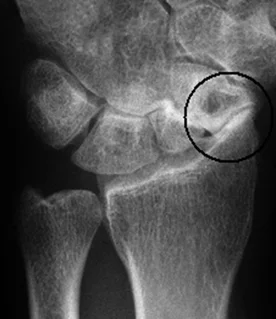

Scaphoid Fracture

- Scaphoid is the common fractured carpal bone

- Fall on the palm of the outstretched hand

- Presents with pain, tenderness in the anatomical snuffbox

- Radiology:

- AP and Lateral not enough

- Need an special scaphoid view